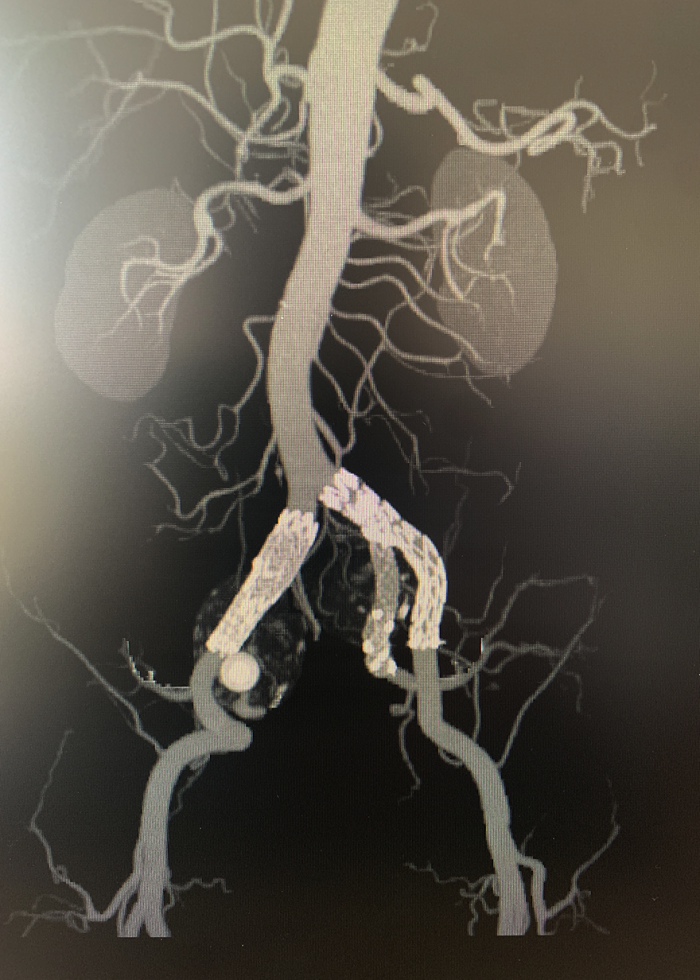

挑战接踵而至,另一位患者73岁的邓老先生所面临的病情则更为复杂与棘手。患者在外院体检时被发现患有腹主动脉瘤,并伴有极为罕见的双侧副肾动脉变异——这些变异血管的直径竟与主肾动脉相当。雪上加霜的是,患者同时存在严重的冠脉狭窄。若采用传统开放手术,心脏无法耐受,风险极高;然而,若不重建这些功能重要的副肾动脉,又将导致肾功能受损。治疗陷入两难,手术迫在眉睫。

为寻求最优方案,患者来到桂林医院求助。医院立即组织多学科会诊,制定了周密的“两步走”方案。首先,由心血管内科驻桂专家方臻飞教授、唐建军教授为其处理冠脉狭窄,提升心脏功能,为大型手术保驾护航;此后,血管外科团队在湘雅名医舒畅教授和本部专家的指导下,迎难而上,挑战腹主动脉瘤的微创治疗。

心脏问题解决后,治疗的“接力棒”交到了血管外科团队手中。团队预先在腹主动脉支架上为副肾动脉开窗并标记,随后在术中精准定位,将导丝导管通过开窗口超选入副肾动脉并成功植入支架,最终造影显示,腹主动脉瘤被完全隔绝,副肾动脉血流通畅,且无内漏。术后,患者肾功能维持良好,平安出院。